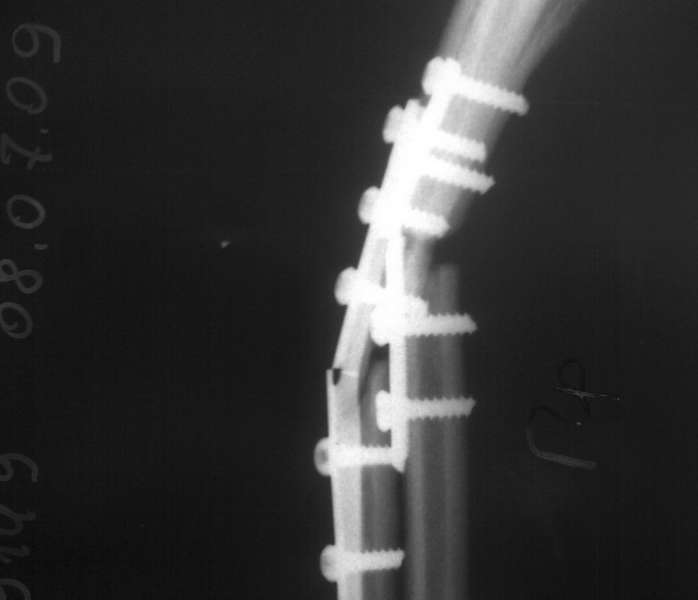

Спасибо коллеги. Выполнили ресинтез реконструкционными пластинами с костной аутопластикой кортикальными трансплантатами с декортикацией.

Кликните для загрузки файла 16072009402[1]

611KB (625938 bytes)

А пластина фиксирована к дистальному отломку лучевой кости двумя винтами?